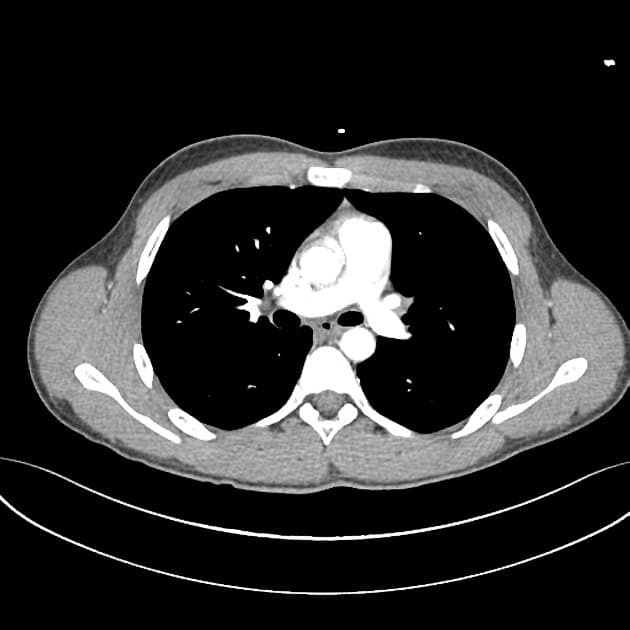

- Buồng thất trái với nội tâm mạc tăng âm và dày lên, thành thất co bóp rất kém (severely hypokinetic walls)

- Hẹp đường ra thất trái (LVOT stenosis) (tỷ lệ RVOT/LVOT: 2.8)

- Không có dòng chảy hướng tâm (antegrade flow) trên siêu âm Doppler màu qua van động mạch chủ và động mạch chủ lên do tắc nghẽn dòng chảy

- Động mạch phổi giãn rõ với dòng chảy hướng tâm, ống động mạch (ductus arteriosus) có dòng chảy ngược chiều (retrograde flow) do không có dòng chảy qua động mạch chủ lên

- Hẹp van hai lá (mitral valve stenosis), đặc trưng bởi tốc độ dòng chảy qua van tăng lên tới 153 cm/giây

Xơ đàn hồi nội tâm mạc (EFE) là một bệnh cơ tim hiếm gặp ở thai nhi và trẻ sơ sinh, đặc trưng bởi tình trạng dày lên lan tỏa của nội tâm mạc, chủ yếu ảnh hưởng đến thất trái. Bệnh được phân loại thành thể nguyên phát (không rõ nguyên nhân, không kèm dị tật tim) hoặc thể thứ phát (liên quan đến các dị tật tắc nghẽn bẩm sinh như hẹp van động mạch chủ, hẹp eo động mạch chủ hoặc dị dạng động mạch vành trái). Trong trường hợp này, các phát hiện như tắc nghẽn đường ra thất trái, hẹp van hai lá và dòng chảy ngược chiều qua ống động mạch gợi ý thể thứ phát do tắc nghẽn nghiêm trọng phía đường ra bên trái tim, dẫn đến thiếu dòng chảy hướng tâm qua động mạch chủ và tuần hoàn bù trừ qua ống động mạch. Tình trạng nội tâm mạc dày và tăng âm là phản ứng thứ phát do thiếu tưới máu mạn tính và tổn thương nội tâm mạc. Chẩn đoán sớm bằng siêu âm tim thai rất quan trọng để theo dõi chức năng tim và lên kế hoạch sinh tại cơ sở có khả năng can thiệp tim mạch sơ sinh.